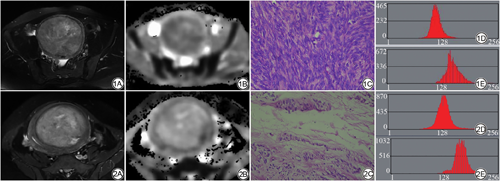

子宫UCL和UL-DT2WI均为高信号,境界清楚,ADC图呈低信号或高信号(图1,2)。2名医师独立勾画VOI,测得组内ICC为0.844。ADC直方图参数分析:UCL组mean、Perc 1%、Perc 10%、Perc 50%、Perc 90%、Perc 99%值低于UL组,variance、skewness值高于UL-D组(P<0.05)。T2WI直方图参数分析:UCL组variance、kurtosis低于UL-D组,Perc 1%值高于UL-D组(P<0.05)。

UCL病理特点为肿瘤中有丰富的平滑肌细胞,瘤细胞分布密集,细胞密度远大于正常肌层组织,同时细胞核较大,呈梭形或卵圆形,排列紧密,而胞质减少,同时肿瘤间质充分也较少[9, 10],而UL-D瘤细胞成分较少,而以间质成分为著,变性瘤体间质水肿明显,肌纤维出现退变,间质为透明样物质取代[7],两者的病理基础差异,为磁共振直方图量化分析鉴别两者提供了可能性。本研究病例组中,子宫UCL组和肌瘤变性组的病灶边界都清晰,无论是T2WI及ADC图像,都能清晰勾勒,本研究采用MaZda软件勾画VOI,操作简便,可重复性高,不同医师勾画的分析参数,其组内相关系数ICC达到了0.844,因此方法容易推广。在单个参数分析中,UCL组ADC参数值性mean、Perc 1%、Perc 10%、Perc 50%、Perc 90%、Perc 99%均低于UL-D组。ADC直方图参数中的低百分位数主要反映肿瘤细胞的密集程度间的差异,与肿瘤侵袭性有关[16],而高百分位数与肿瘤内坏死、纤维化及微血管性等因素相关[17],本组参数特征表明UCL较UL-D相比具有更大的细胞密集程度,细胞外间隙较小,水分子扩散受限,符合子宫UCL细胞丰富、间质少的病理特征[18]。同时,本研究中UCL组ADC高百分位参数低于UL-D组,表明UL-D组较UCL组更容易发生囊变、坏死,导致直方图参数中高百分位数值增高。同样在T2WI直方图参数中,UL-D方差值(variance)以及kurtosis高于UCL组,表明UL-D瘤体具有更大的异质性,亦与UL-D囊变、坏死导致信号局限性增高、图像信号更加混杂相关。如上表明肌瘤伴变性肿瘤内部具有较大的异质性,而富于细胞肿瘤内部具有较大的同质性。本研究结果与Valdes-Devesa等[15]的结果一致,与Gerges等[19]的研究结果略有差异,后者发现T2WI直方图参数对鉴别子宫肉瘤和UL-D有较大的效能,可能是由于该研究纳入的病例组是普通型的子宫肌瘤,在T2WI以低信号为主,与本研究纳入的T2WI为高信号的子宫肌瘤不同有关。